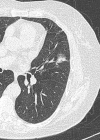

Results: A nonsolid nodule was identified in 2392 (4.2%) of 57,496 baseline screenings, and pathologic pursuit led to the diagnosis of 73 cases of adenocarcinoma. A new nonsolid nodule was identified in 485 (0.7%) of 64,677 annual repeat screenings, and 11 had a diagnosis of stage I adenocarcinoma; none were in nodules 15 mm or larger in diameter. Nonsolid nodules resolved or decreased more frequently in annual repeat than in baseline rounds (322 [66%] of 485 vs 628 [26%] of 2392, P < .0001). Treatment of the cases of lung cancer was with lobectomy in 55, bilobectomy in two, sublobar resection in 26, and radiation therapy in one. Median time to treatment was 19 months (interquartile range [IQR], 6-41 months). A solid component had developed in 22 cases prior to treatment (median transition time from nonsolid to part-solid, 25 months). The lung cancer-survival rate was 100% with median follow-up since diagnosis of 78 months (IQR, 45-122 months).

Conclusion: Nonsolid nodules of any size can be safely followed with CT at 12-month intervals to assess transition to part-solid. Surgery was 100% curative in all cases, regardless of the time to treatment.